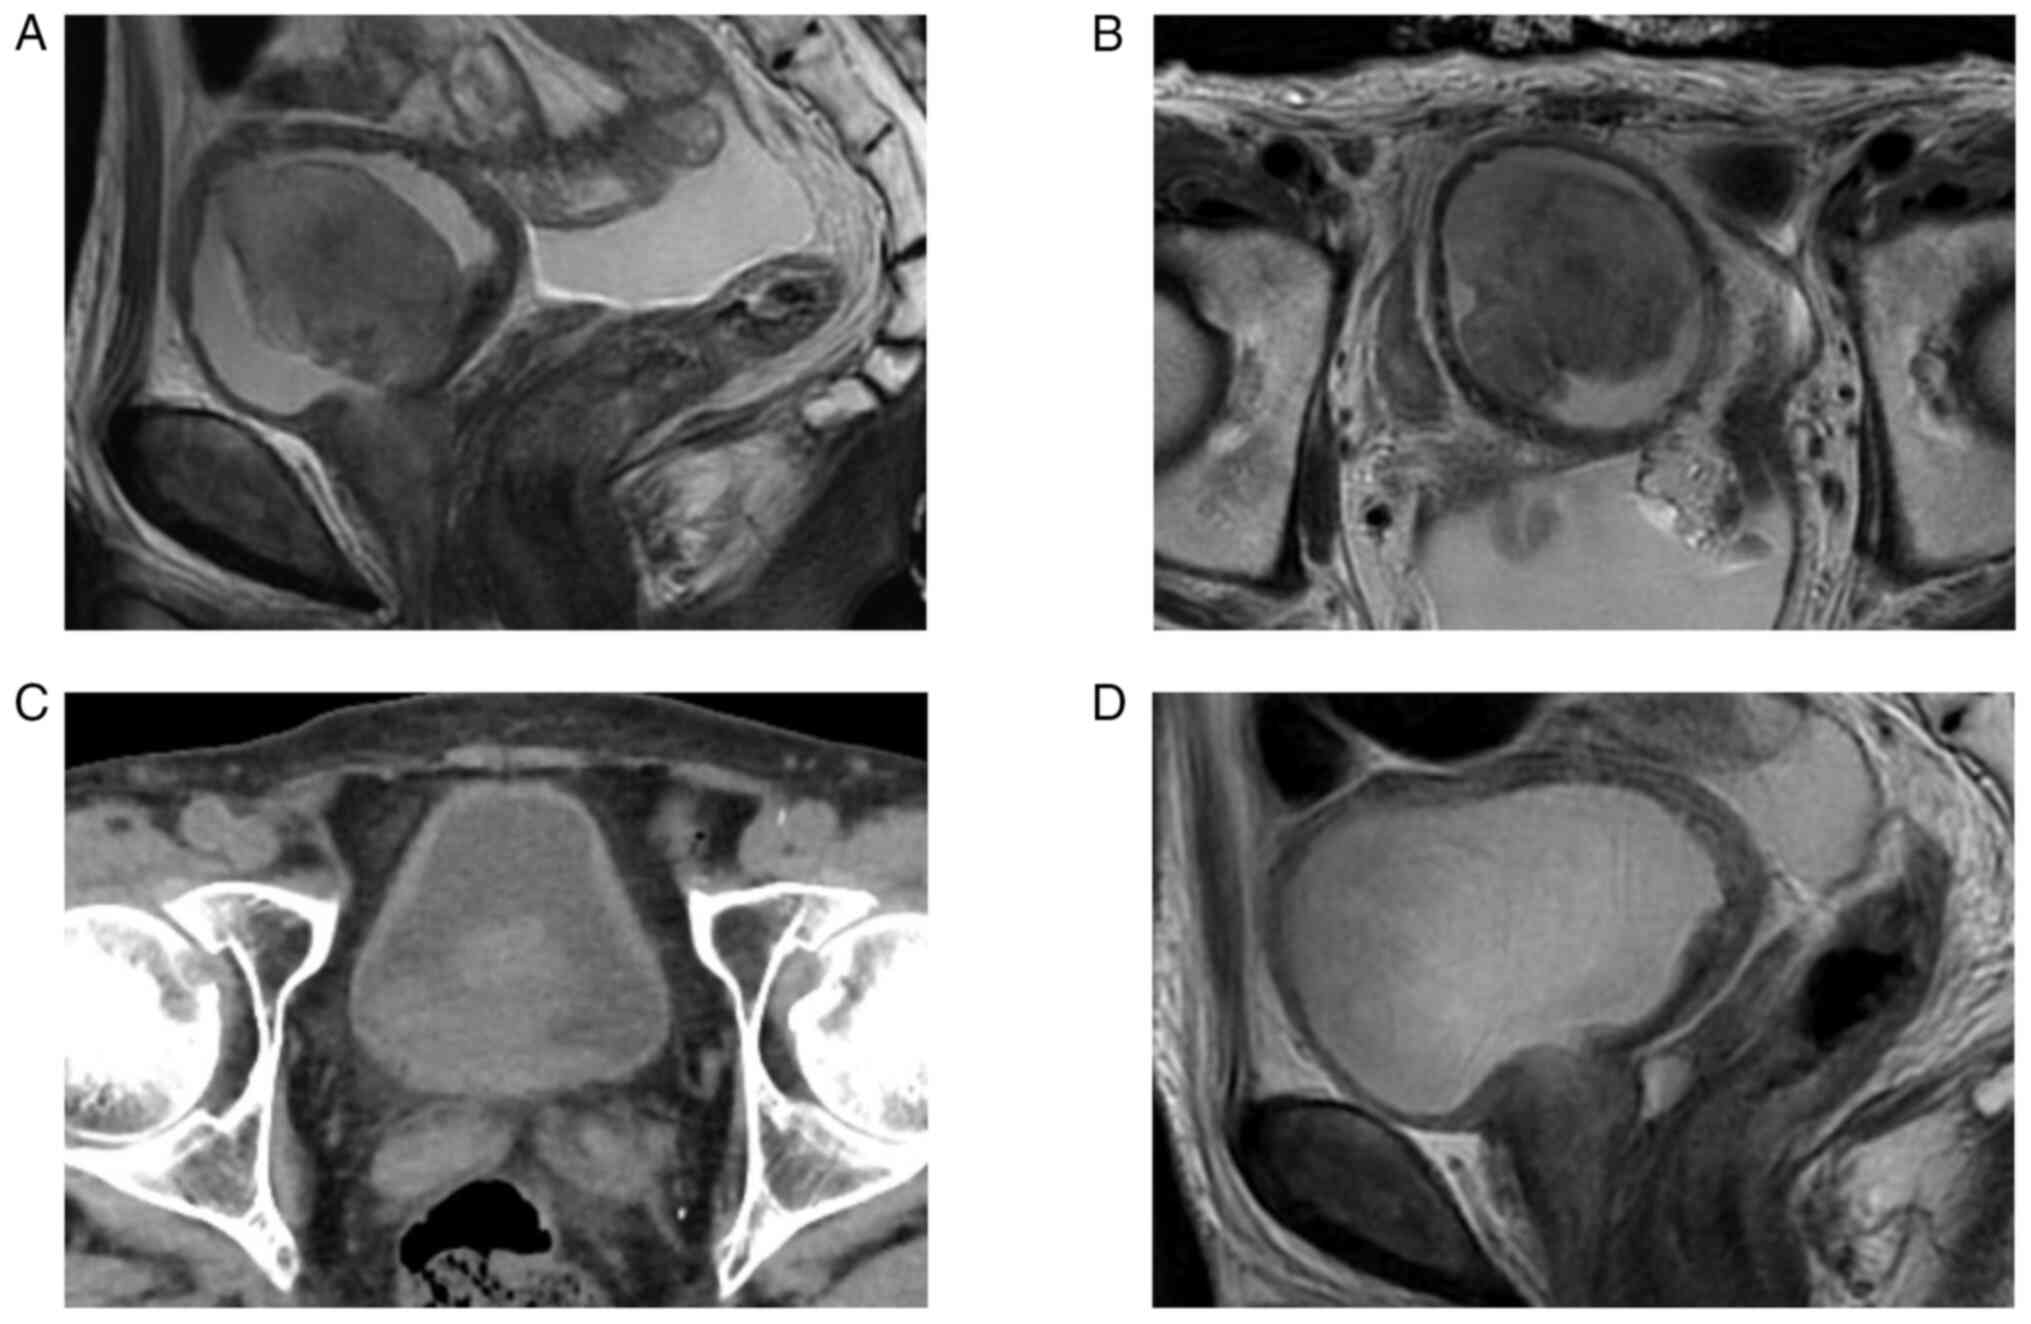

Urothelial carcinoma of the bladder with osteoclast‑like giant cells (UCOGCs) is rare among the subtypes of poorly differentiated urothelial carcinoma. Its clinical significance and optimal treatment are unknown, and few reports on genomic analysis of UCOGCs have been reported. Detailed analysis including genetic analysis for rare type variants of cancer could be a foothold for further research. The present case describes the case of a 75‑year‑old man who presented with a non‑papillary bladder tumor 56 mm in diameter showing gross hematuria and pain on voiding. Following transurethral resection of the bladder tumor, the pathological diagnosis was invasive UCOGCs. Neoadjuvant chemotherapy and radical cystectomy were performed with the resected tumor pathologically diagnosed as invasive UCOGCs, high grade, pT3b, pN1. The present study also analyzed the genomic features using a cancer panel test. The panel test noted six gene alterations (PIK3CA p.E542K, HRAS p.G13R, ARAF copy number amplification, CDKN2A copy number loss, TP53 p.E285V, ARID1A p.S90Pfs*11) and telomerase reverse transcriptase (TERT) promoter variant. Accumulation of knowledge from molecular‑based testing is anticipated to determine precise treatment for rare cancer.

Figure 1